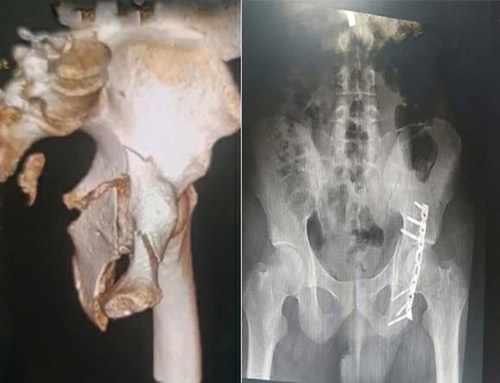

وأضاف د. علاء أن المريض بعد استقرار حالته الصحية خضع إلى تثبيت الكسر في الجهة اليسرى من الحوض بواسطة شريحة وبراغي معدنية، وبعد أسبوع أُجريت له عملية أخرى لإصلاح الرباط الجانبي والأنسجة الداخلية للركبة اليمنى، بالإضافة إلى عملية زراعة رباط متصالب أمامي بواسطة المنظار، واستغرقت العملية الأولى نحو «3» ساعات فيما استمرت الثانية ساعتين.